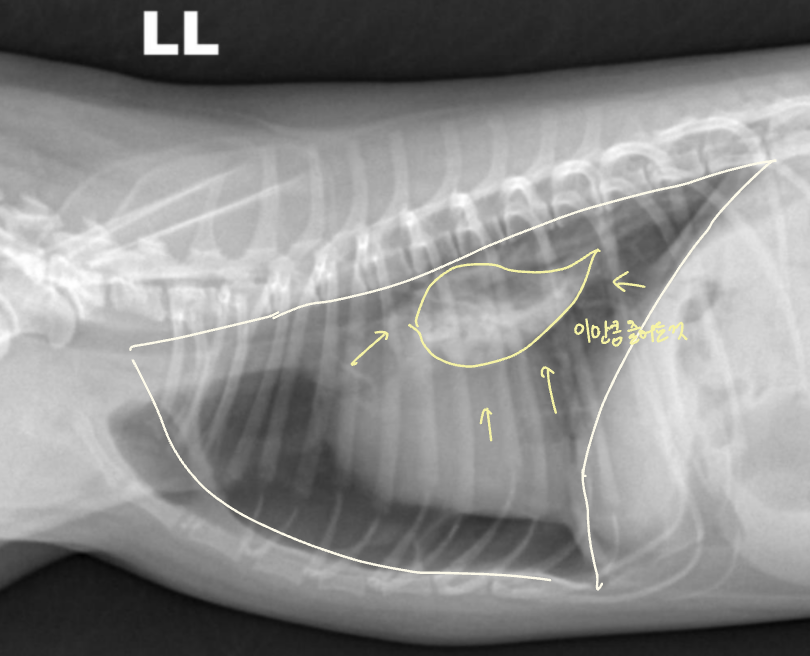

| Radiographic signs interlobar fissure ๋๊ป๊ฒ ๊ด์ฐฐ๋๊ณ , ํ๋ฒฝ์ด ๋จ์ด์ ธ ๋๊ฐ ๊ฒ์ฒ๋ผ ๋ณด์ | Radiographic signs ์ฌ์ฅ์ด ๋ ์๊ณ , ํ๊ฐ ์ชผ๊ทธ๋ผ๋ฆ | |

| - Interlobar fissure widening - Lung retraction - Pleural wall thickening - Scallop sign - Cardiac effacement - Blunt angle | - Retraction of pleural surface - Collapsed lung (โ opacity ์ฆ๊ฐ) | |

![]() | ![]() | |

![]() ![]() | ![]() ![]() | |

![]() |